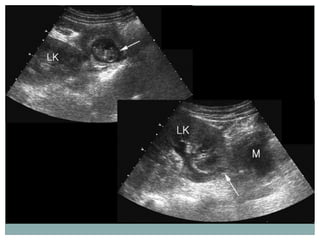

Embarazo ectópico abdominal

   Infrecuente. Aborto tubario??

   Implantación en la cavidad peritoneal. Se

excluye las trompas, ovarios y localizaciones

intraligamentarias.

   Mas frecuente en tratamientos de

reproducción asistida.

   Representan el 1.4% de los embarazos

ectópicos

   Asociado a hemorragia y alta mortalidad

materna.

   Se pueden observar fuera de la pelvis en

abdomen superior

   Extraperitoneales!!!